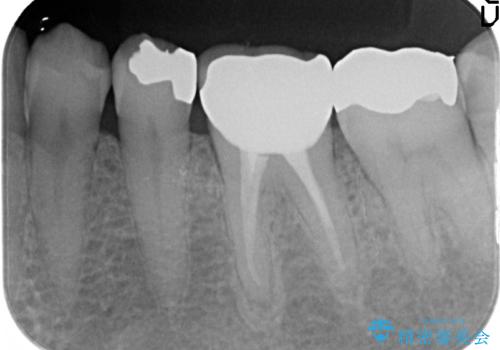

- 左下の奥歯が激しく痛むので診て欲しいといらっしゃった方の症例です。

他院で相談したところ抜歯を提案されたが、歯を抜かずに済む方法はないかと当院にいらっしゃいました。

検査の結果左下6に根尖病変を認めたため、再根管治療を行いました。

その後症状の消失を確認し、オールセラミッククラウンによる補綴を行いました。